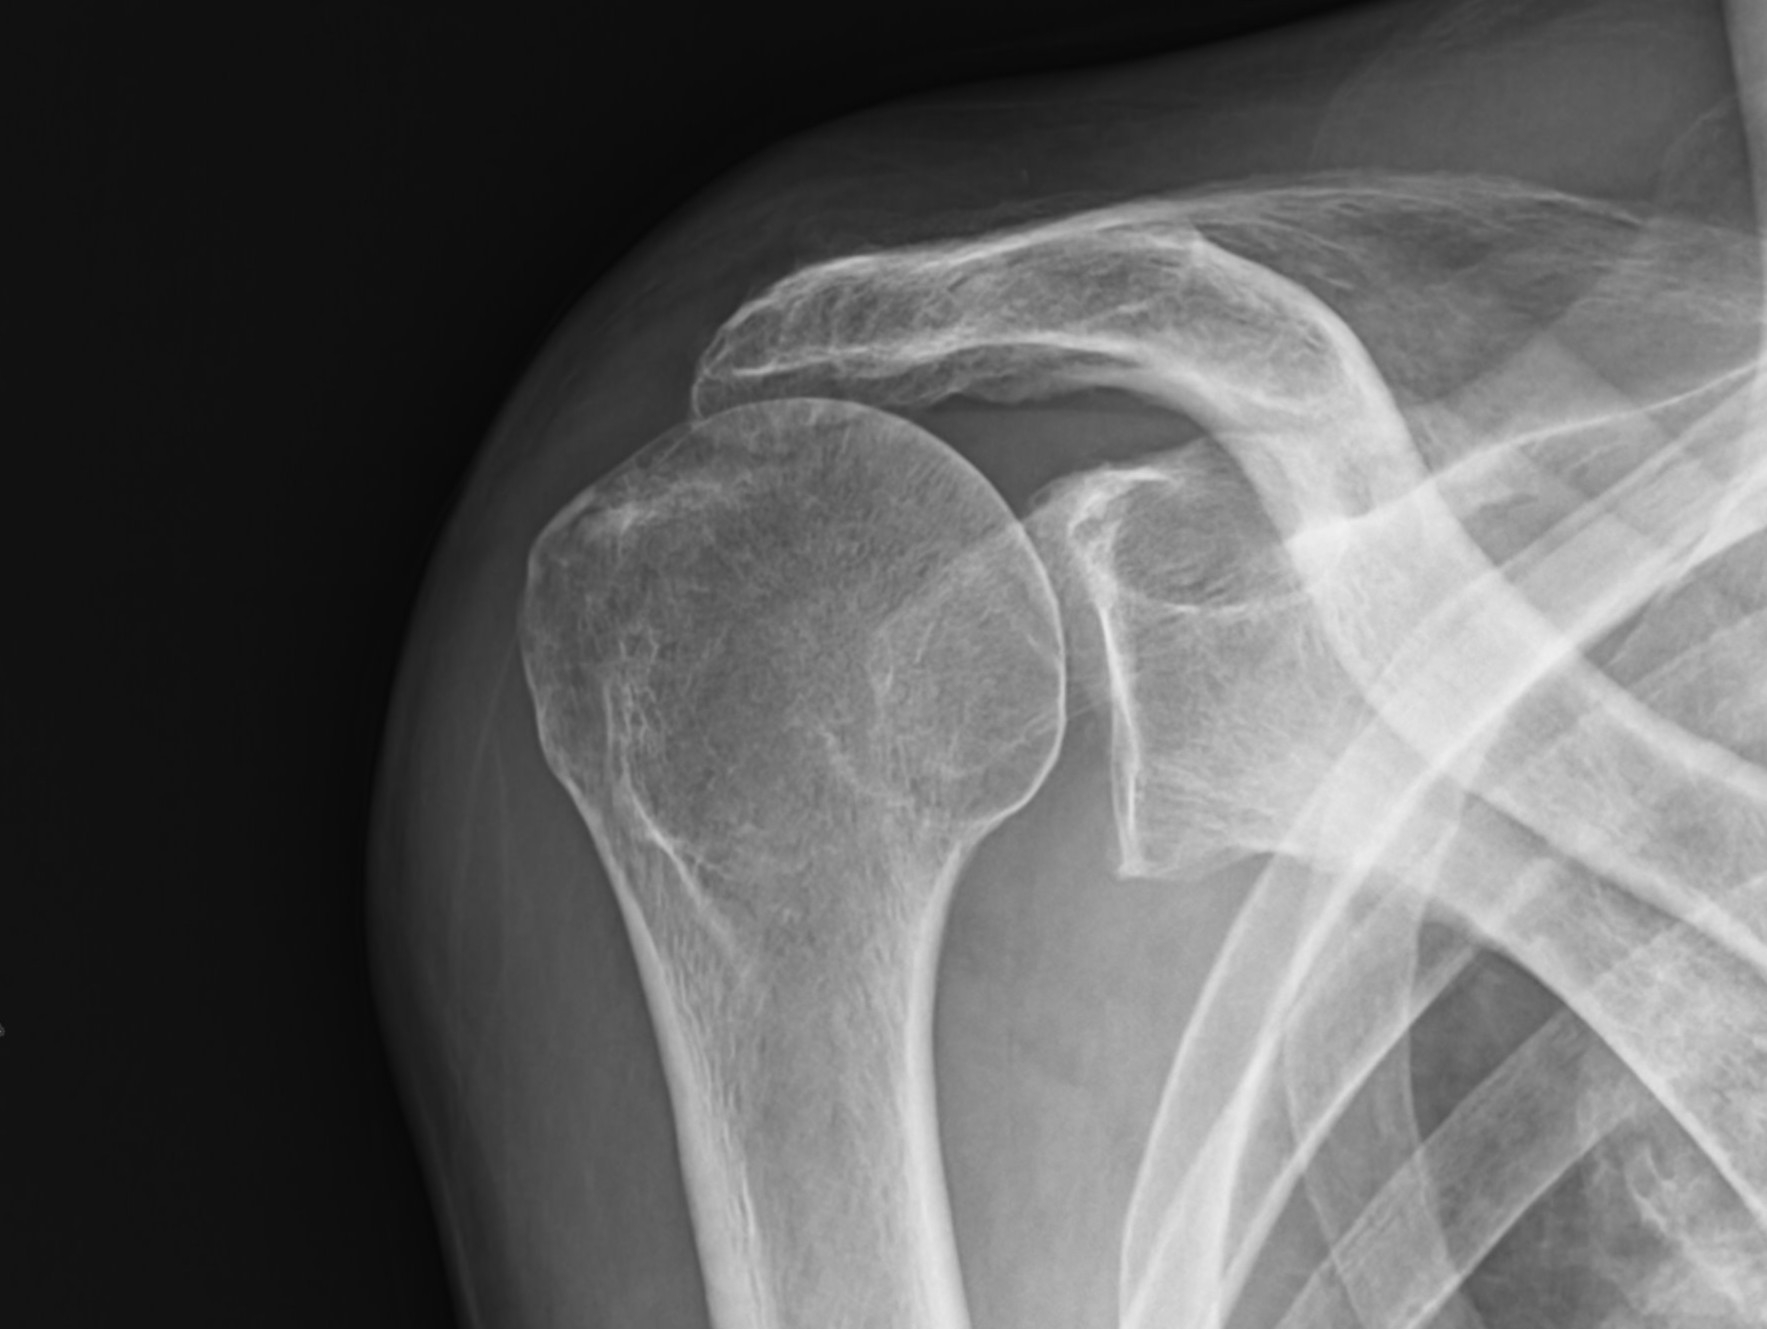

高齢者の広範囲腱板断裂に対するリバース人工肩関節

術前レントゲン写真